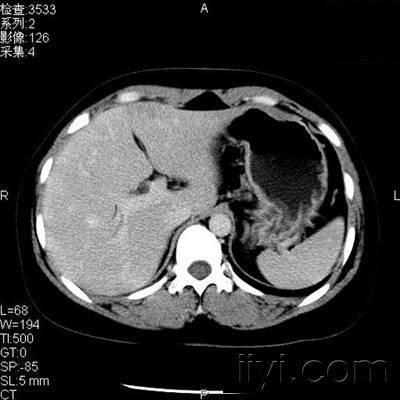

患者,女性,体检发现肝左叶低密度病变2天

门静脉期